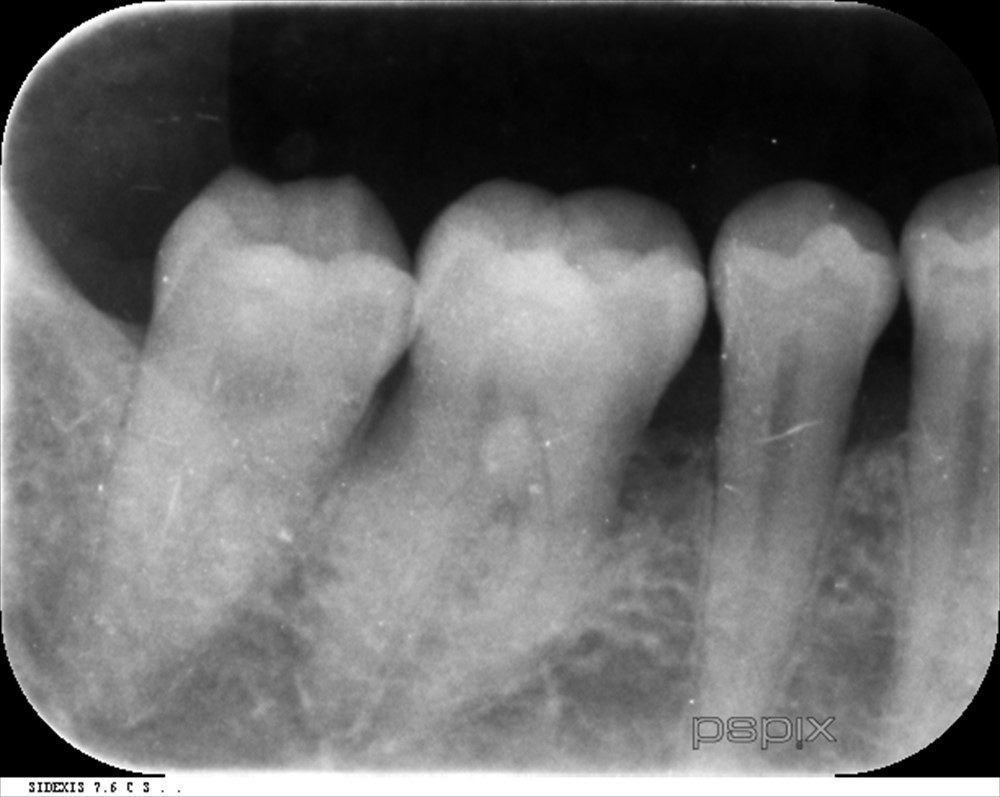

レントゲン

骨の量も全額的に少なく、下の前歯は抜けていました。

右下の6番 膿が出ていました。。。

ここは垂直的に骨が無くなっていました。ポケットは7mm。

術後6ヶ月レントゲン↓

術前↓

再生が認められます。